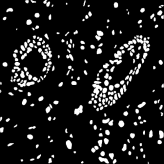

Microscopic image segmentation is a challenging task, wherein the objective is to assign semantic labels to each pixel in a given microscopic image. While convolutional neural networks (CNNs) form the foundation of many existing frameworks, they often struggle to explicitly capture long-range dependencies. Although transformers were initially devised to address this issue using self-attention, it has been proven that both local and global features are crucial for addressing diverse challenges in microscopic images, including variations in shape, size, appearance, and target region density. In this paper, we introduce SA2-Net, an attention-guided method that leverages multi-scale feature learning to effectively handle diverse structures within microscopic images. Specifically, we propose scale-aware attention (SA2) module designed to capture inherent variations in scales and shapes of microscopic regions, such as cells, for accurate segmentation. This module incorporates local attention at each level of multi-stage features, as well as global attention across multiple resolutions. Furthermore, we address the issue of blurred region boundaries (e.g., cell boundaries) by introducing a novel upsampling strategy called the Adaptive Up-Attention (AuA) module. This module enhances the discriminative ability for improved localization of microscopic regions using an explicit attention mechanism. Extensive experiments on five challenging datasets demonstrate the benefits of our SA2-Net model. Our source code is publicly available at \url{https://github.com/mustansarfiaz/SA2-Net}.